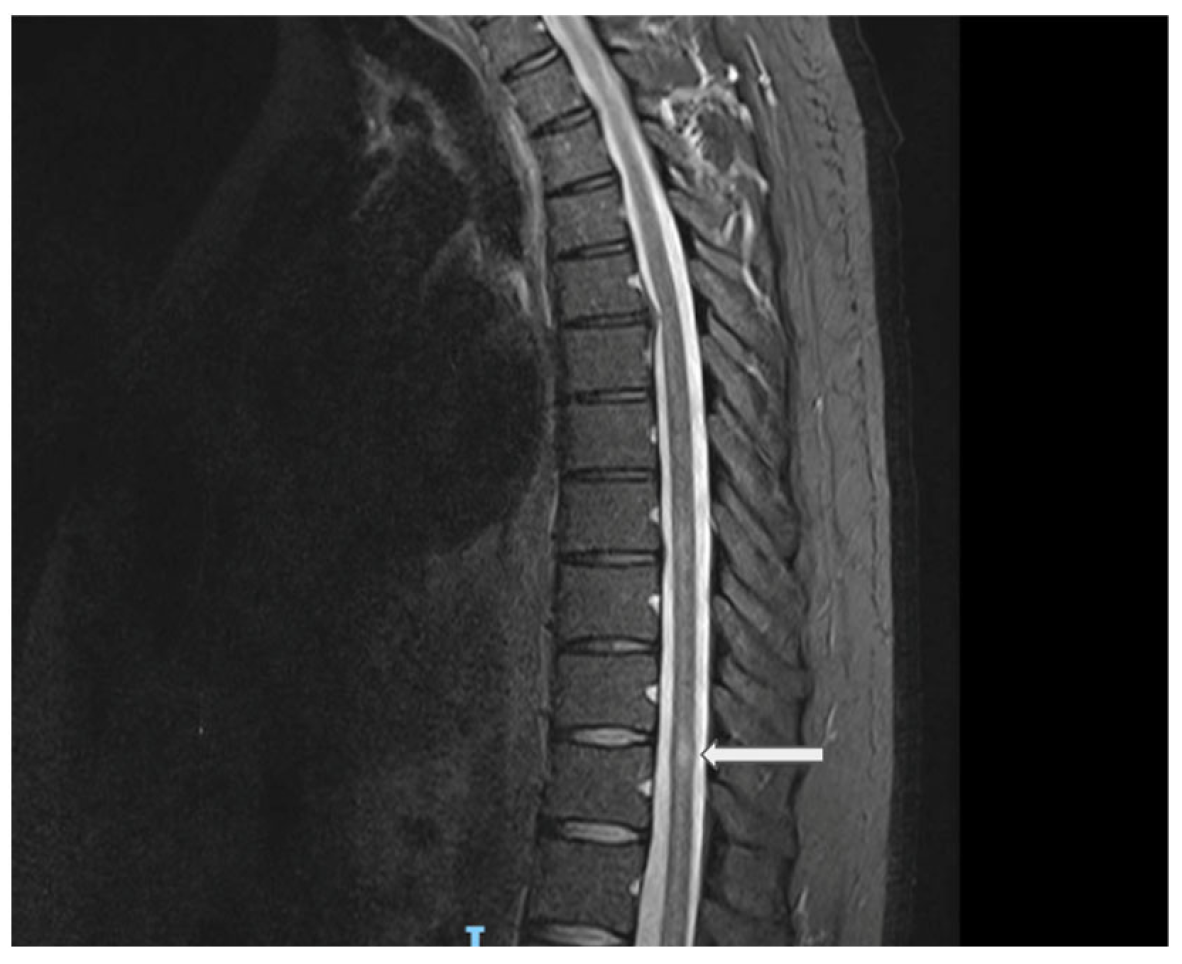

| Present Case | 42/M | m.11778G>A (MT-ND4) | Painful acute ON sequential involvement over 1 year | Right-optic-nerve enhancement, no brain MS lesions; later thoracic T11 myelitis; normal brain MRI | Initial CSF normal; later OCBs positive | Rituximab, idebenone | Unique sequence: LHON genetically confirmed before demyelinating event; MRI enhancement atypical for LHON |